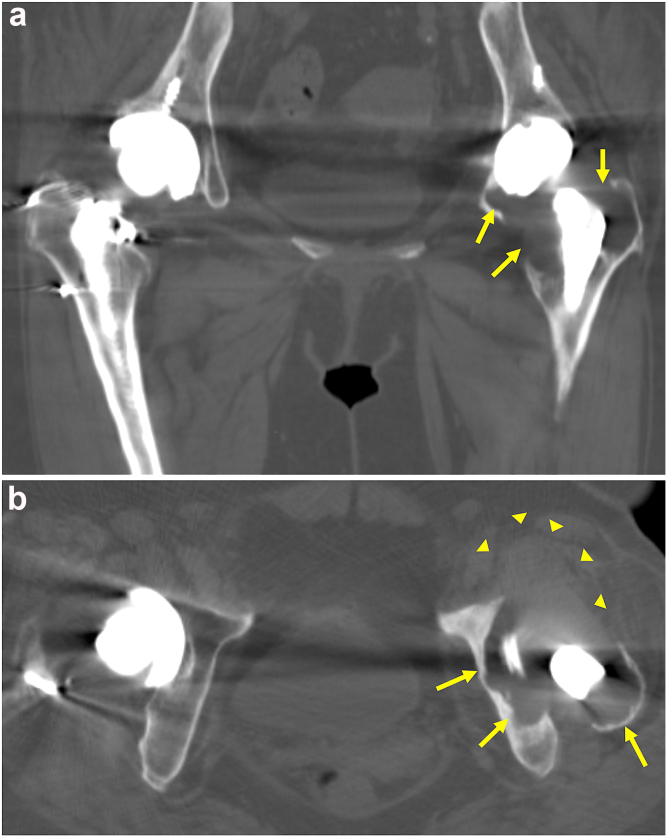

Figure 4.

Coronal (a) and axial (b) CT images showing massive osteolysis (arrows) and soft-tissue mass (arrowheads) around the cup and the proximal stem.

A 54-year-old female patient underwent a primary THA at an outside institution for the diagnosis of secondary osteoarthritis in the left hip. The third-generation alumina CoC bearing with a diameter of 28 mm was implanted with a self-locking TriAD HA acetabular cup and Super Secur-Fit HA femoral stem. All these implants were from Stryker (Mahwah, NJ). A right primary CoC THA using the same implant devices was performed for secondary osteoarthritis at 5 years after the left primary THA. Osteolytic lesions were found in the proximal regions of the stem (Gruen zones 1 and 7 [16]) and around the cup (DeLee and Charnley zone 3 [17]) in an anteroposterior radiograph taken at 6-year follow-up after the left primary THA (Fig. 1a). The previous study suggested a desirable combined anteversion within a range of 25°–50° [18]. A high combined anteversion angle of 75° (stem: 40° and cup: 35°) was noted in the left hip by computed tomography imaging (Fig. 2). In contrast, the combined anteversion on the right hip was within the ideal range (45°; stem: 25° and cup: 20°). A radiological sign of cup loosening was found with a progressive osteolytic lesion (Fig. 1b). Metal artifact reduction sequence magnetic resonance imaging identified a 42 × 40 × 64-mm soft-tissue mass around the femoral neck (Fig. 3) that had been asymptomatic for several years. The patient experienced mild pain in her left hip at 10 years postoperatively and was referred to our institution because of aggravated pain and the need for revision THA using allogeneic bone grafting for treating the large bone defect associated with periprosthetic massive osteolysis formation (Fig. 4).